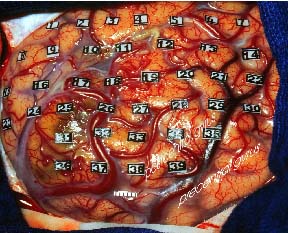

Das freigelegte Hirn wird dazu mit sterilen Plättchen markiert. Jeder Punkt wird anschließend elektrisch stimuliert.

Im Bereich des motorischen Systems erhält man aus der Muskulatur der Extremitäten ein Signal. Mit dessen Hilfe kann während der gesamten Operation am offenen Hirn die Funktion der für die Körperbewegung wichtigen Zentren überwacht werden.